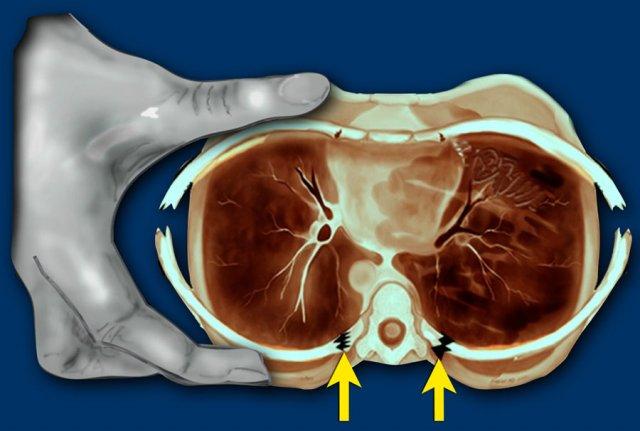

Hình ảnh

CT cho thấy hình ảnh rách tụy trong trường hợp bạo hành trẻ em.

Rách gan trong trường hợp bạo hành trẻ em